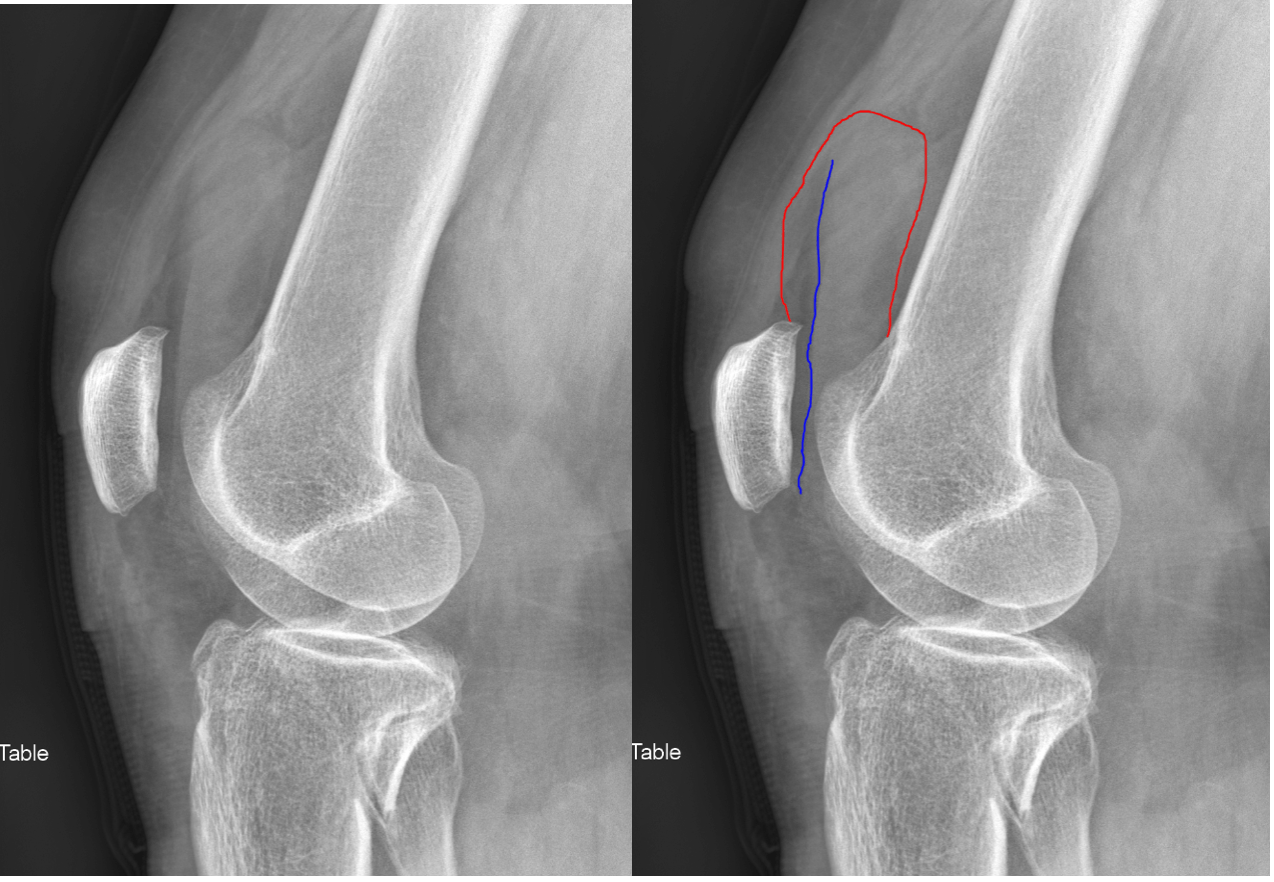

Accuracy of CrossTable Lateral Knee Radiography for Evaluation of Large Size Knee Joint Effusion Health care providers might refer to this condition as an. Knee effusions can arise from traumatic injuries, such as ligament tears or fractures, inflammatory conditions like. Four major ligaments support the knee, which is the largest. A swollen knee occurs when excess fluid collects in or around your knee joint. Knee effusion, sometimes called water on the knee, occurs when. Large Size Knee Joint Effusion.

Musculoskeletal (MSK) Xray Interpretation OSCE Guide Geeky Medics Large Size Knee Joint Effusion There are certainly other signs of knee joint effusions such as anterior displacement of the patella, but these are only reliably seen on large. Four major ligaments support the knee, which is the largest. A knee effusion refers to an abnormal fluid accumulation within the knee joint. Joint effusion is swelling of the tissues in or around your joint because. Large Size Knee Joint Effusion.

kneejointeffusion Don't the Bubbles Large Size Knee Joint Effusion There are certainly other signs of knee joint effusions such as anterior displacement of the patella, but these are only reliably seen on large. Joint effusion can cause a puffy appearance to your joints along with symptoms like pain and. Common causes include arthritis and injury to knee. Knee effusion, sometimes called water on the knee, occurs when excess fluid. Large Size Knee Joint Effusion.